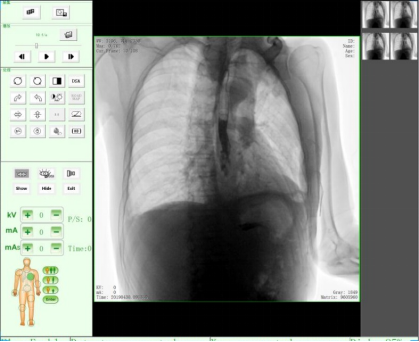

三、医学用途,医用X射线机作为医学诊断重要的设备之一,目前市面上医用X射线机种类主要有DR、CR、C形臂、乳腺机、胃肠机、口腔CBCT等医疗器械。设备依据X射线的穿透作用、差别吸收、感光作用和荧光作用,利用人体各组织的密度和厚度不同,通过检测图像阴影浓淡的对比,结合临床表现、化验结果和病理诊断,即可判断人体某一部位/内部器官是否正常。此类X光机广泛应用于医疗机构与场所,为相关单位提供了快速的医疗诊断。